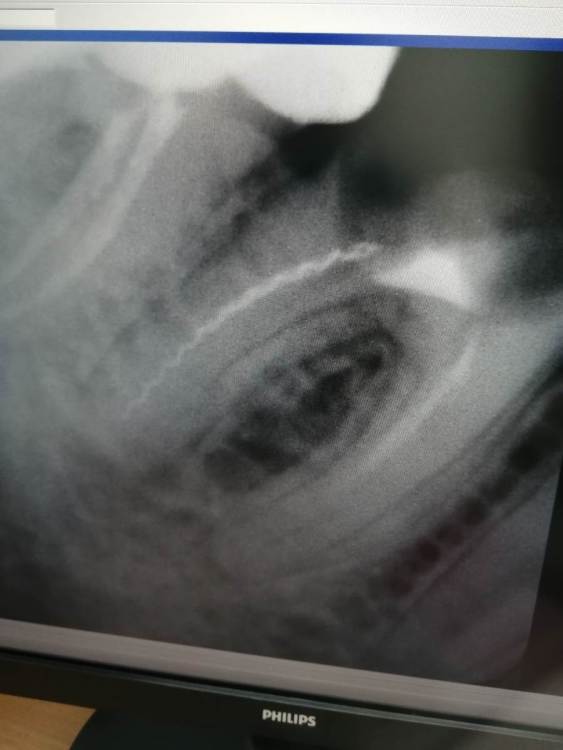

Кирова зоя Опубликовано 29 марта, 2023 Поделиться Опубликовано 29 марта, 2023 Одни мне говорят что это инструмент забыли. Другие говорят что это не инструмент, не игла. Подскажите пожалуйста, что это такое в канале Ссылка на комментарий

АнтонТЛТ Опубликовано 29 марта, 2023 Поделиться Опубликовано 29 марта, 2023 Каналонаполнитель 1 1 Ссылка на комментарий

red_butler Опубликовано 30 марта, 2023 Поделиться Опубликовано 30 марта, 2023 судя по степени разрушения, что в канале уже не важно 1 2 Ссылка на комментарий

Кирова зоя Опубликовано 1 апреля, 2023 Автор Поделиться Опубликовано 1 апреля, 2023 Видно ли на рентгене что есть трещина? Ссылка на комментарий

IvanK Опубликовано 1 апреля, 2023 Поделиться Опубликовано 1 апреля, 2023 2 часа назад, Кирова зоя сказал: Видно ли на рентгене что есть трещина? Здравствуйте, если Вам будет легче смириться с тем, что зуб нужно удалять, то трещину можно предположить.. Ссылка на комментарий